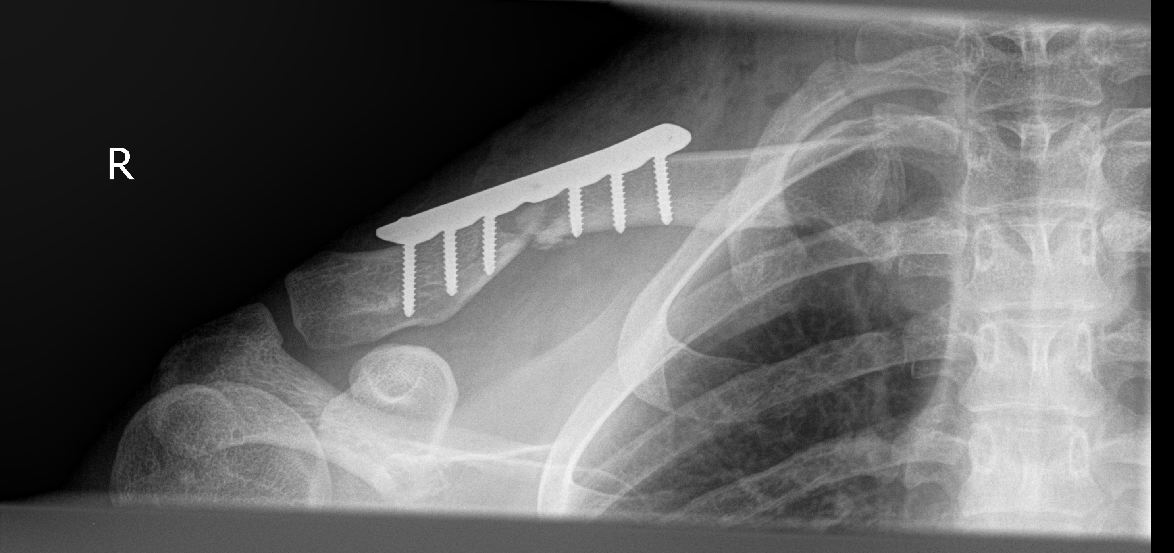

Habe jetzt ne schöne Titanplatte auf dem rechten Schlüsselbein die mit insgesamt 6 Schrauben befestigt ist.

Im Anhang habe ich mal 2 Röntgenbilder hochgeladen, habe die von dem Krankennhaus auf CD bekommen.

Weil die beiden Bruchenden sich dann halt schon übereinander gelegt hatten (sieht man gut auf dem ersten Bild) musste halt eine Platte drauf die das ganze in die richtige Stellung bringt.